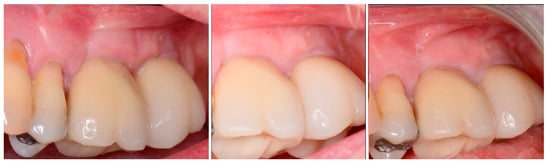

The patient returned at 10 weeks post-2nd-implant placement and a screw-retained restoration was placed on the 1st molar and a radiograph was obtained (Figure 13, left). Impressions were obtained and the restoration on the 2nd molar was placed at a subsequent appointment. Soft tissue was healthy at placement of the restoration on the 2nd molar and no marginal inflammation was noted at either site (Figure 14, left). Soft tissue at the 1-year recall remained healthy and lacking in inflammation (Figure 14, middle). At a 2-year recall, a radiograph was obtained and bone was noted to be stable at both implants (Figure 13, right). Soft tissue at the 2-year recall remained stable and no change in marginal position was noted compared to initial restoration placement (Figure 14, right).

Figure 14.

Soft tissue at placement of the restoration on the 2nd molar (left), at 1 year post-restoration (middle) and at 2 years post-restoration (right) demonstrating maintenance of the keratinized tissue long term.